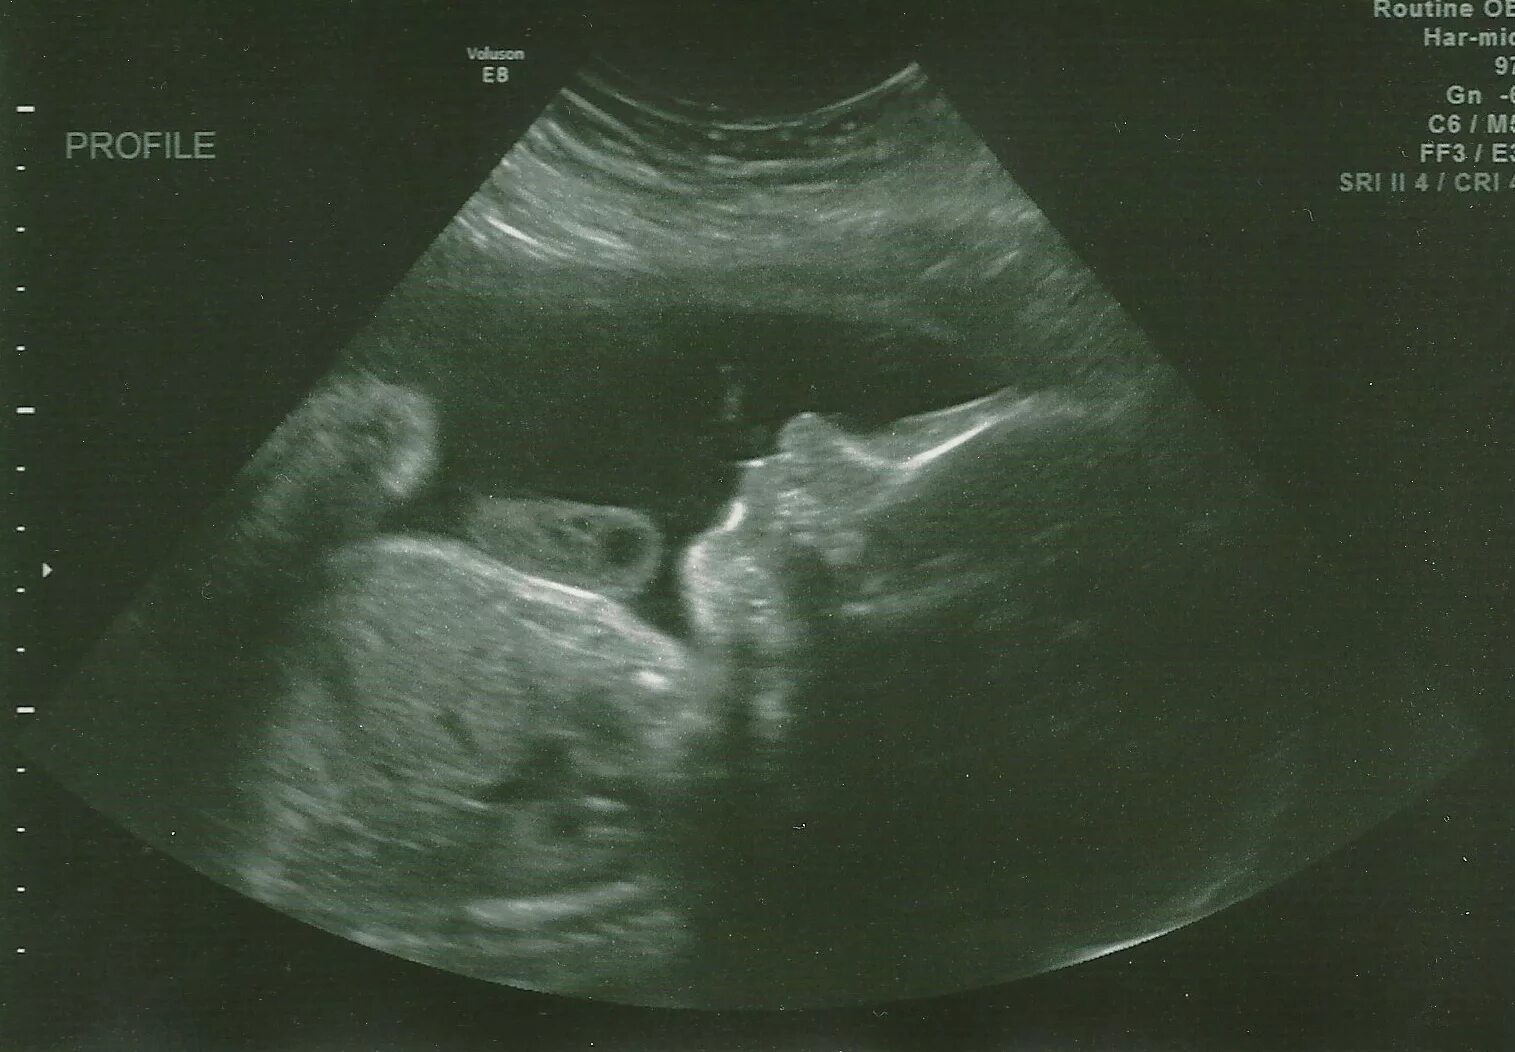

Ребенок в утробе 31 неделя